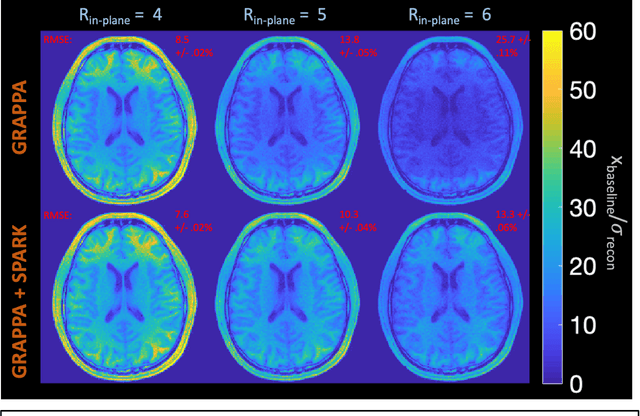

Purpose: To develop a scan-specific model that estimates and corrects k-space errors made when reconstructing accelerated Magnetic Resonance Imaging (MRI) data. Methods: Scan-Specific Artifact Reduction in k-space (SPARK) trains a convolutional neural network to estimate k-space errors made by an input reconstruction technique by back-propagating from the mean-squared-error loss between an auto-calibration signal (ACS) and the input technique's reconstructed ACS. First, SPARK is applied to GRAPPA and demonstrates improved robustness over other scan-specific models. Then, SPARK is shown to synergize with advanced reconstruction techniques by improving image quality when applied to 2D virtual coil (VC-) GRAPPA, 2D LORAKS, 3D GRAPPA without an integrated ACS region, and 2D/3D wave-encoded imaging. Results: SPARK yields 1.5 - 2x RMSE reduction when applied to GRAPPA and improves robustness to ACS size for various acceleration rates in comparison to other scan-specific techniques. When applied to advanced parallel imaging techniques such as 2D VC-GRAPPA and LORAKS, SPARK achieves up to 20% RMSE improvement. SPARK with 3D GRAPPA also improves RMSE performance and perceived image quality without a fully sampled ACS region. Finally, SPARK synergizes with non-cartesian, 2D and 3D wave-encoding imaging by reducing RMSE between 20 - 25% and providing qualitative improvements. Conclusion: SPARK synergizes with physics-based reconstruction techniques to improve accelerated MRI by training scan-specific models to estimate and correct reconstruction errors in k-space.